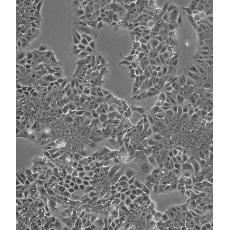

HCT-15 [HCT15]

中文名稱 人結(jié)直腸腺癌細(xì)胞

組織來(lái)源 結(jié)腸腺癌;男性

生長(zhǎng)特性 adherent

形態(tài)特征 epithelial

細(xì)胞描述 HCT-15 cells are CSAp negative(CSAp-).The cells are positive for keratin by immunoperoxidase staining.